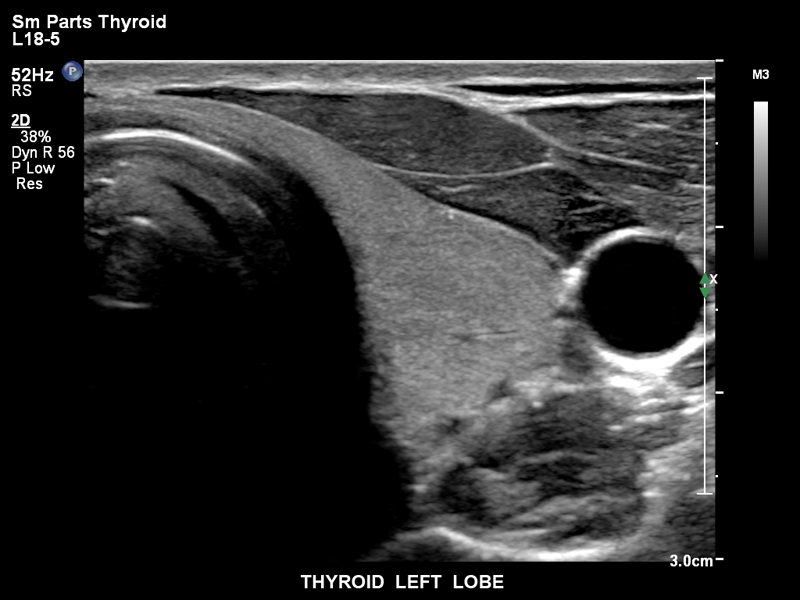

Щитовидная железа, левая доля, L18-5